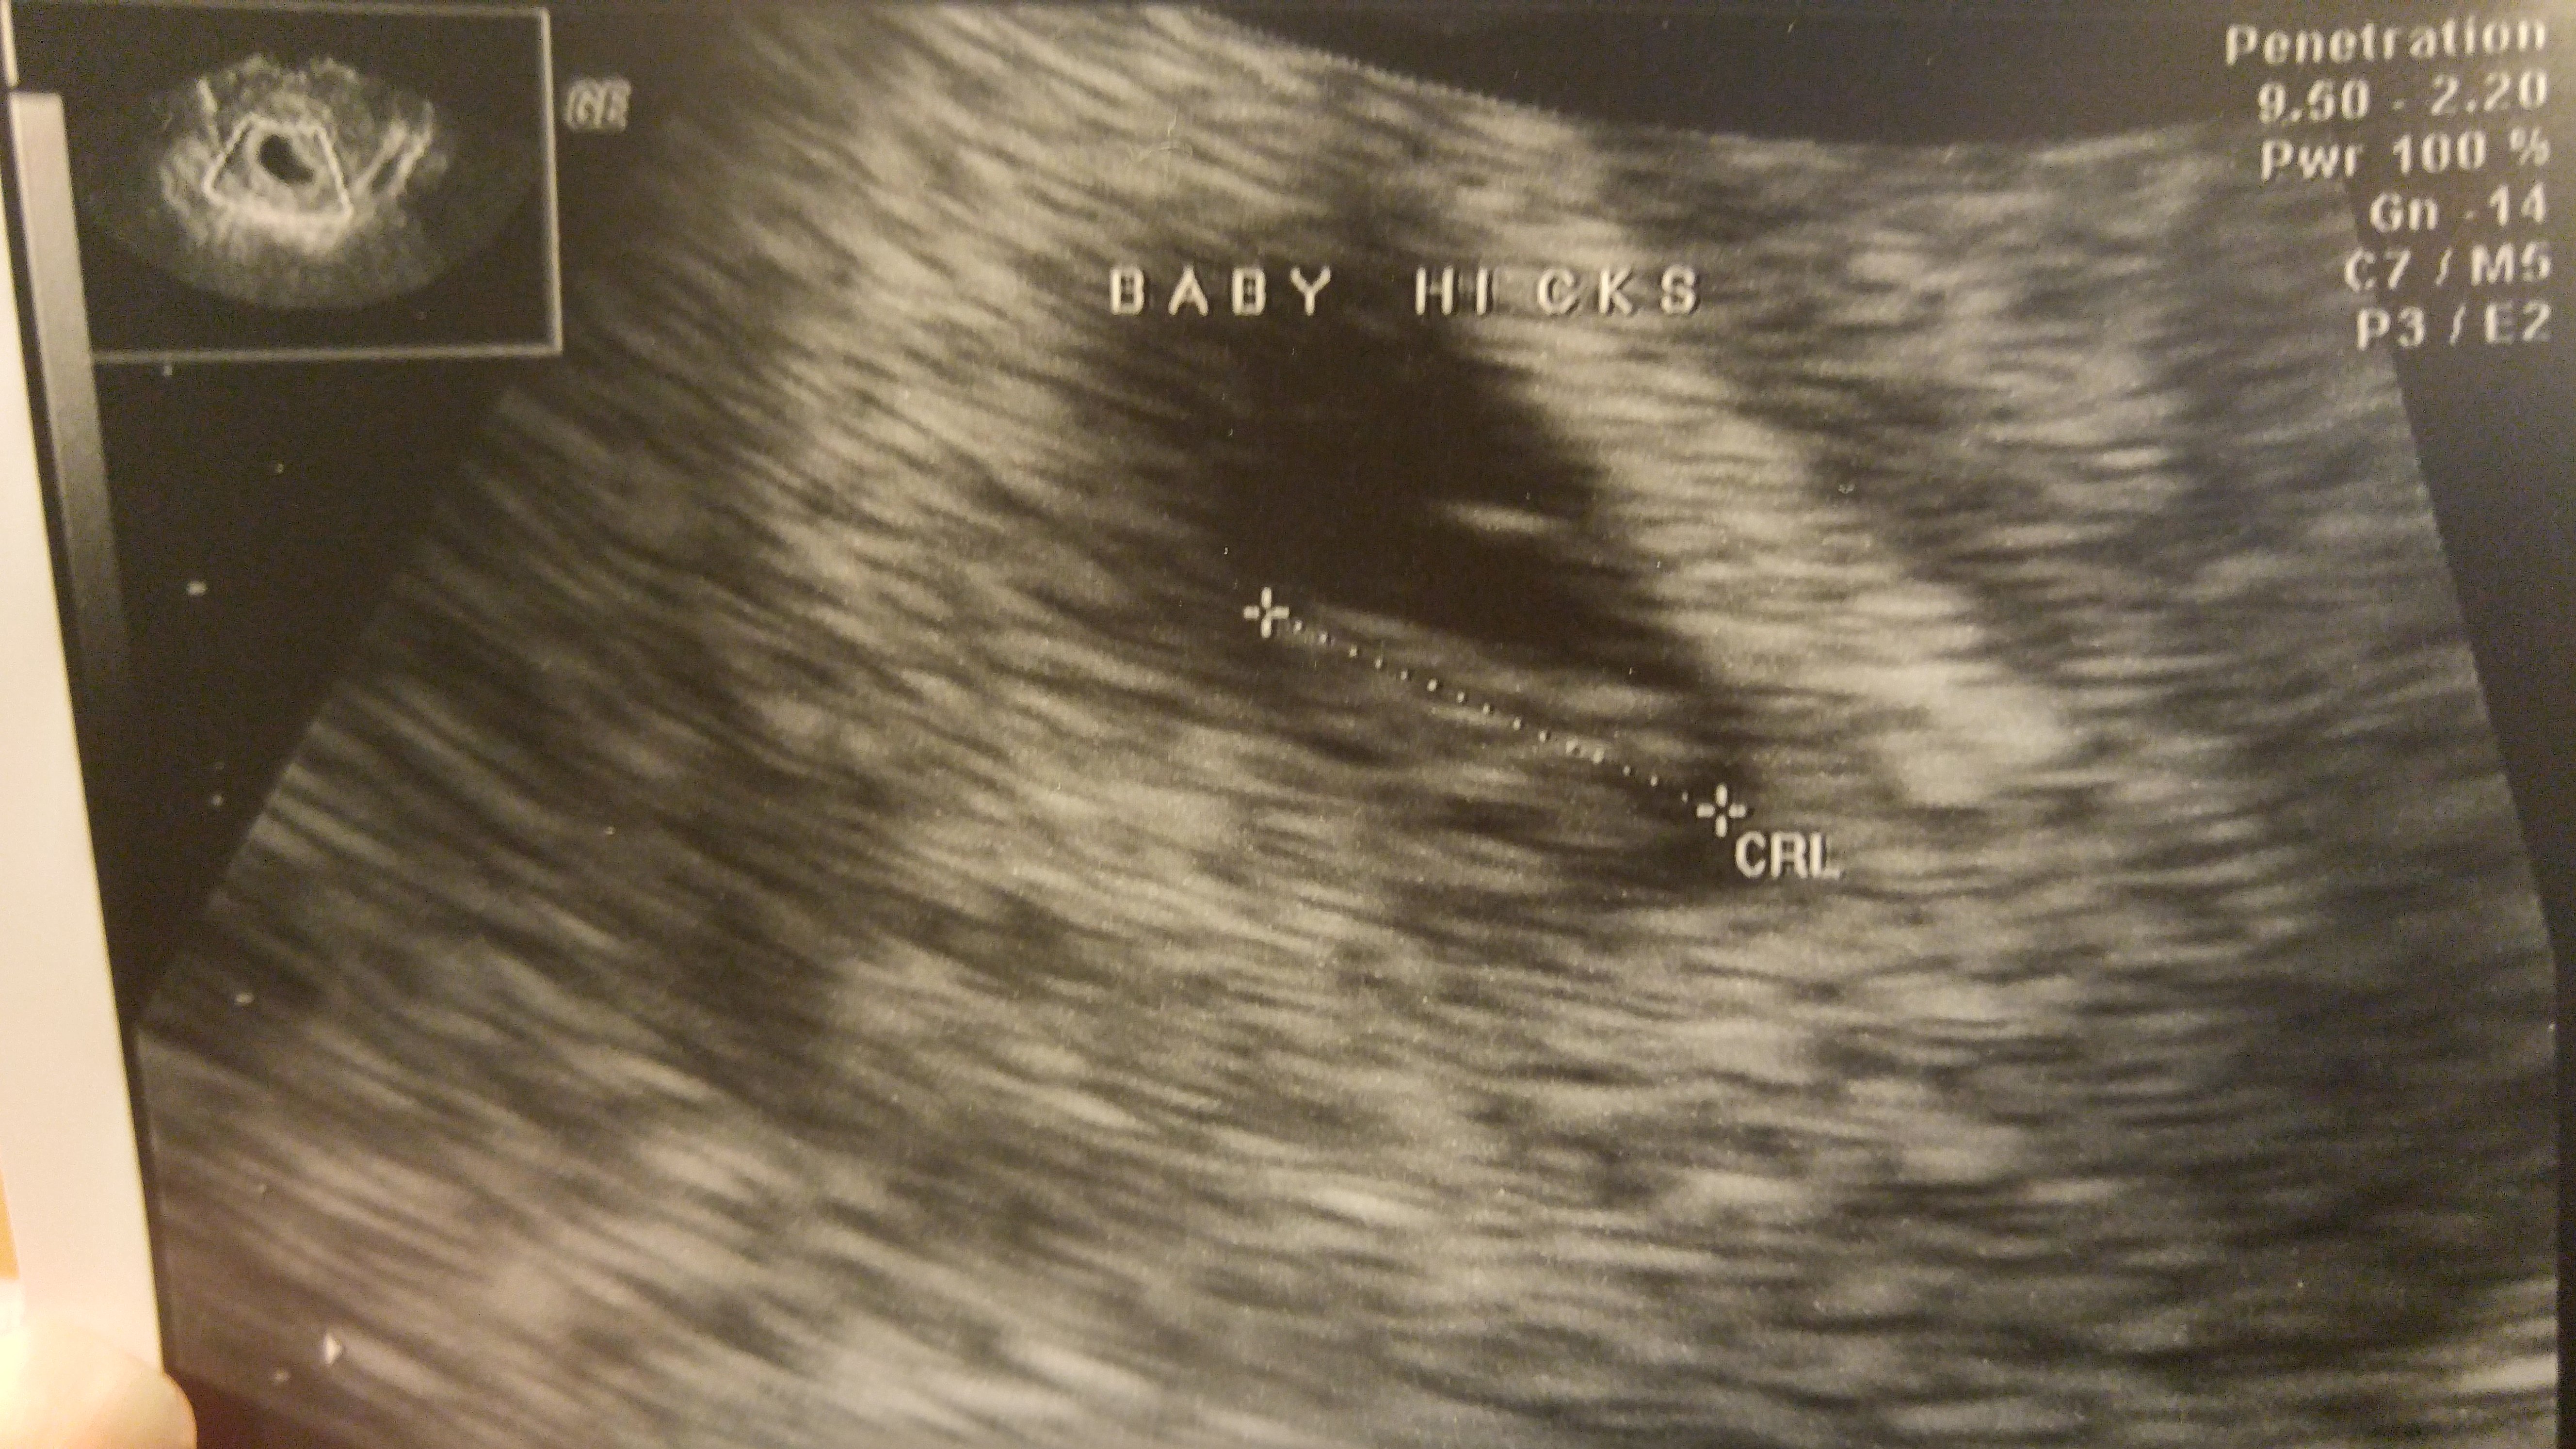

I had my second u/s on Tuesday at 8 weeks and 6 days. The baby is still measuring three days behind but they have not changed my edd. It was great to see how big the baby has gotten and to see its heart still beating. I go back on the 23 for some genetic testing and I get an u/s at that appointment, which was a great surprise to hear that. The equipment at the new place I have to go to is so much better than what my doctor has. Im hoping I can actually hear the heart beat at that appointment. I have not been able to hear it or to know how many bpm it is. But here is my little bean!

Btw I have no clue what those white lines are and neither does my doctor.